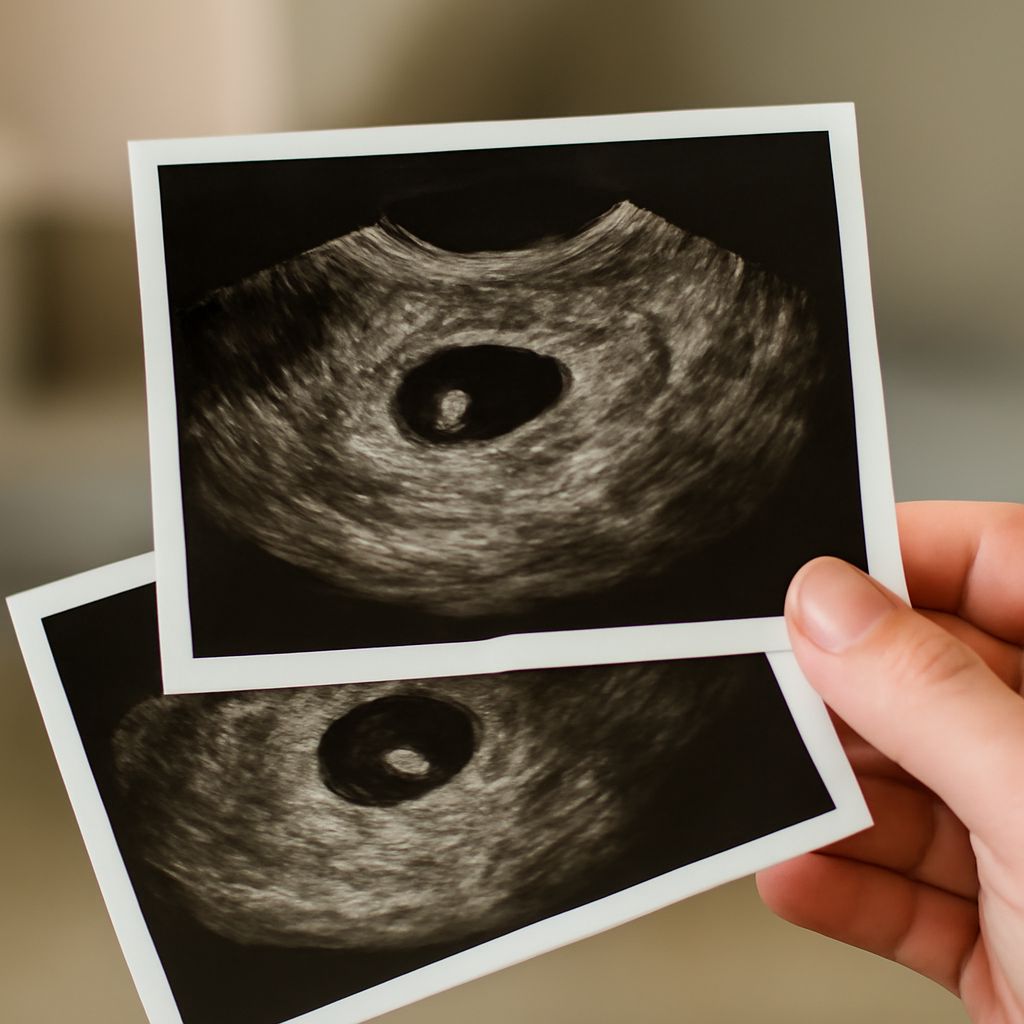

At 5 weeks, the ultrasound images primarily show the gestational sac and possibly the yolk sac. The embryo itself may not yet be visible, but these initial structures are crucial indicators of a developing pregnancy.

Reading these early images requires an understanding of the expected structures. The ultrasound at 5 weeks may show a small, dark gestational sac within the uterus. While details are sparse, the correct positioning and presence of the sac are positive signs.

What to Expect in the Image

The ultrasound image at this stage might only show the gestational sac and possibly the yolk sac, with the embryo not being readily visible. However, the presence of these early structures is indicative of normal early development.